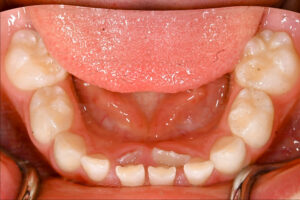

まるでサメの歯のように2列に並んで生えている様子を見て、「これって異常?」「歯並びが悪くなってしまうのでは?」と焦ってしまう親御さんは非常に多いです。 実はこれ、歯科用語では**「異所萌出(いしょほうしゅつ)」**などと呼ばれ、特に下の前歯によく見られる現象です。決して珍しいことではありません。

しかし、顎の骨の中で永久歯の位置が少しずれていたり、顎が小さくてスペースが足りなかったりすると、永久歯が乳歯の根っこを溶かさずに、別の場所(多くは舌側)からひょっこりと顔を出してしまうのです。 こうなると、乳歯は根っこがしっかり残ったままなので、なかなか抜けません。これが「二枚歯」の状態です。